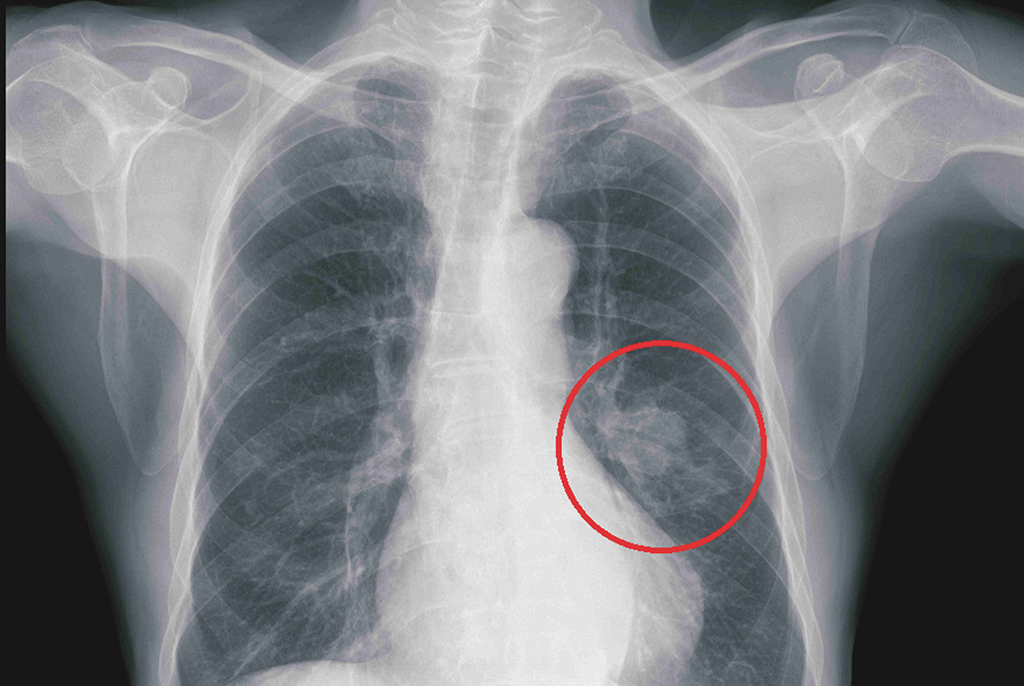

呂俊佑醫師指出,一位84歲男性被診斷為左側肺癌,腫瘤組織檢查顯示存在EGFR突變,經超過一年的第三代標靶藥物治療,患者的療效良好,且副作用控制在可接受範圍內。

84歲男性患者,被診斷為左側肺癌,腫瘤組織檢查顯示存在EGFR突變。

84歲男性患者,經過超過一年的第三代標靶藥物治療,療效良好。